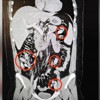

Şüpheli S.A.’nın hastanede çekilen röntgeninde midesinde 44 kapsül olduğu tespit edildi.

Eskişehir Cumhuriyet Başsavcılığı’nın talimatıyla cerrahi müdahaleye alınan S.A.’nın midesindeki 44 kapsül çıkarıldı.